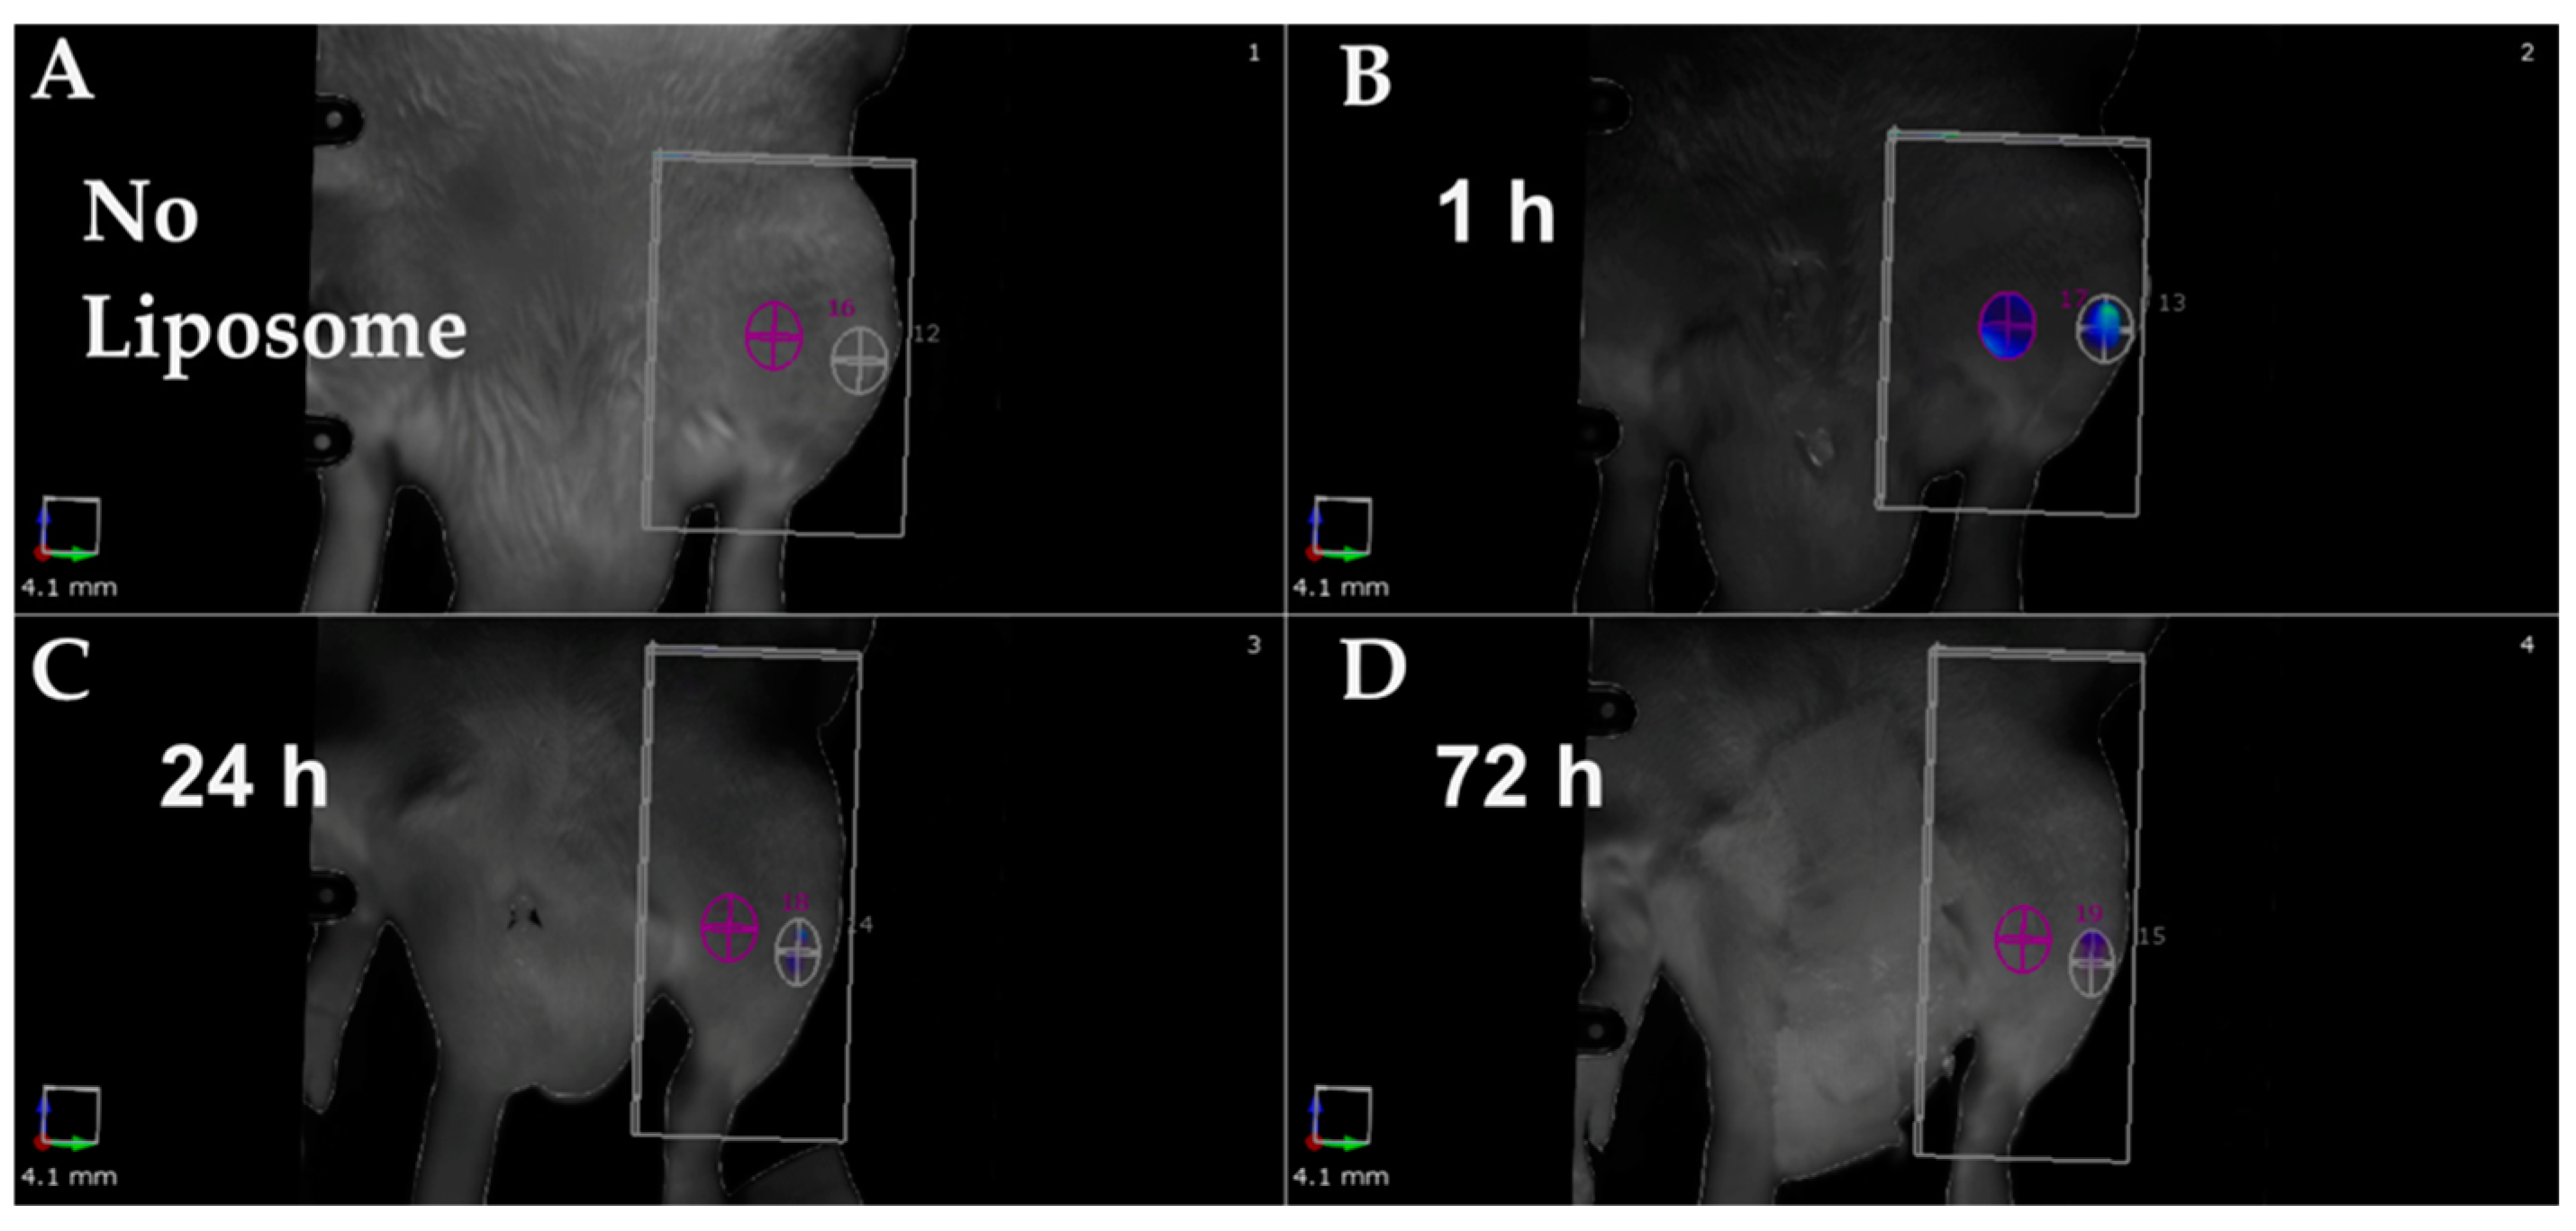

- Riyaz, S.; Helmholz, H.; Medina, T.P.; Medina, O.P.; Will, O.; Sun, Y.; Wiese, B.; Glüer, C.-C.; Willumeit-Römer, R. Exploring the Usability of α-MSH-SM-Liposome as an Imaging Agent to Study Biodegradable Bone Implants In Vivo. Int. J. Mol. Sci. 2023, 24, 1103. [Google Scholar] [CrossRef] [PubMed]

- Helmholz, H.; Will, O.; Penate-Medina, T.; Humbert, J.; Damm, T.; Luthringer-Feyerabend, B.; Willumeit-Römer, R.; Glüer, C.; Penate-Medina, O. Tissue responses after implantation of biodegradable Mg alloys evaluated by multimodality 3D micro-bioimaging in vivo. J. Biomed. Mater. Res. Part A 2021, 109, 1521–1529. [Google Scholar] [CrossRef]